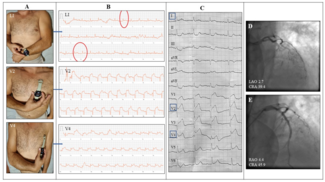

A 67-year-old man with a history of smoking, hyperlipidemia, and hypertension complained of central chest pain radiating to his left arm for 2 hours and contacted the attending cardiologist. Based on medical history and symptom description,...